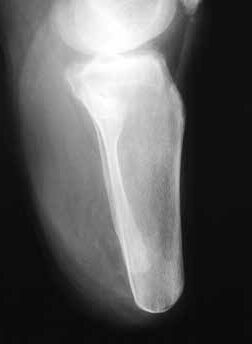

Sehr lange Unterschenkelstümpfe (kurz oberhalb der Spongiosa der distalen Tibia) sind auf die Dauer wegen der Gefahr zunehmender trophischer Störungen über die Jahre auch bei sehr geringem Endkontakt in der Prothese problematisch (Abb. 11). Viele Jahre scheint ein langer US-Stumpf gut versorgbar zu sein, wenn die Amputation im Kindesalter stattfindet und wenn Tibia- und Fibulaende sich fast auf gleicher Höhe befinden und somit eine breitere Auflagefläche für den Endkontakt darstellen (Abb. 12). Gewebe und arterielle Durchblutung stellen sich offenbar im Kindesalter auch besser auf die Gesamtsituation ein. Allgemein gilt aber: Der beste Unterschenkelstumpf ist der, der mit Muskulatur unter physiologischer Vorspannung gedeckt ist.